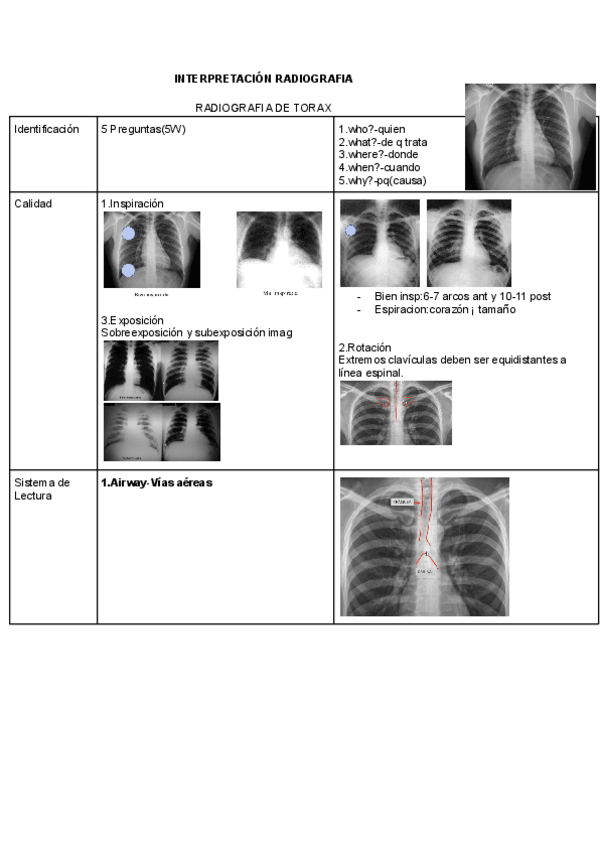

He publicado nuevos apuntes de 3º Cuidados Especiales: Apuntes-radio.pdf

resumen-tema-rayos.pdf